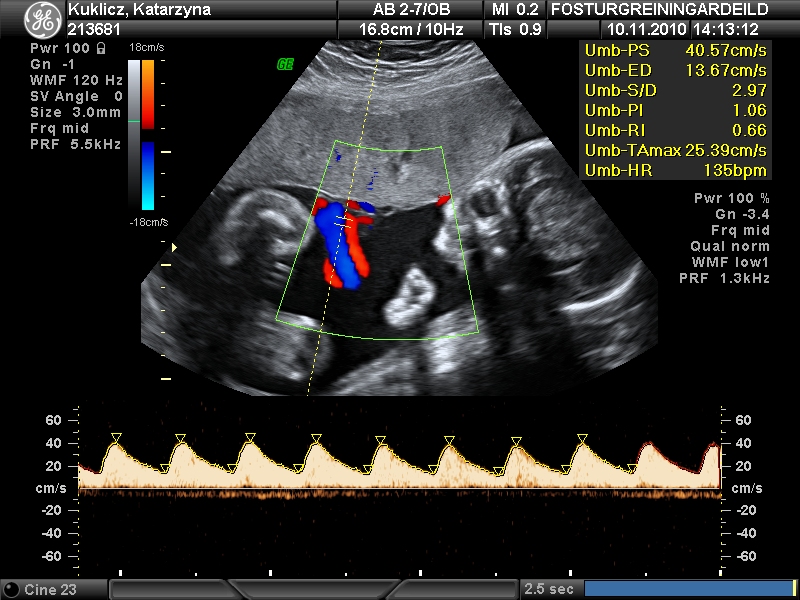

Vaxtarskerðing getur verið tvenns konar, snemmkomin eða síðkomin. Til að greina á milli þess hvort um er að ræða raunverulega vaxtarskerðingu (IUGR) eða aðeins að fóstrið sé smávaxið (SGA) er ráðlagt að nota flæðismælingar.

Hægt er að mæla flæði í naflastreng, miðhjarnaæð (MCA) í höfði barns og legslagæðar.